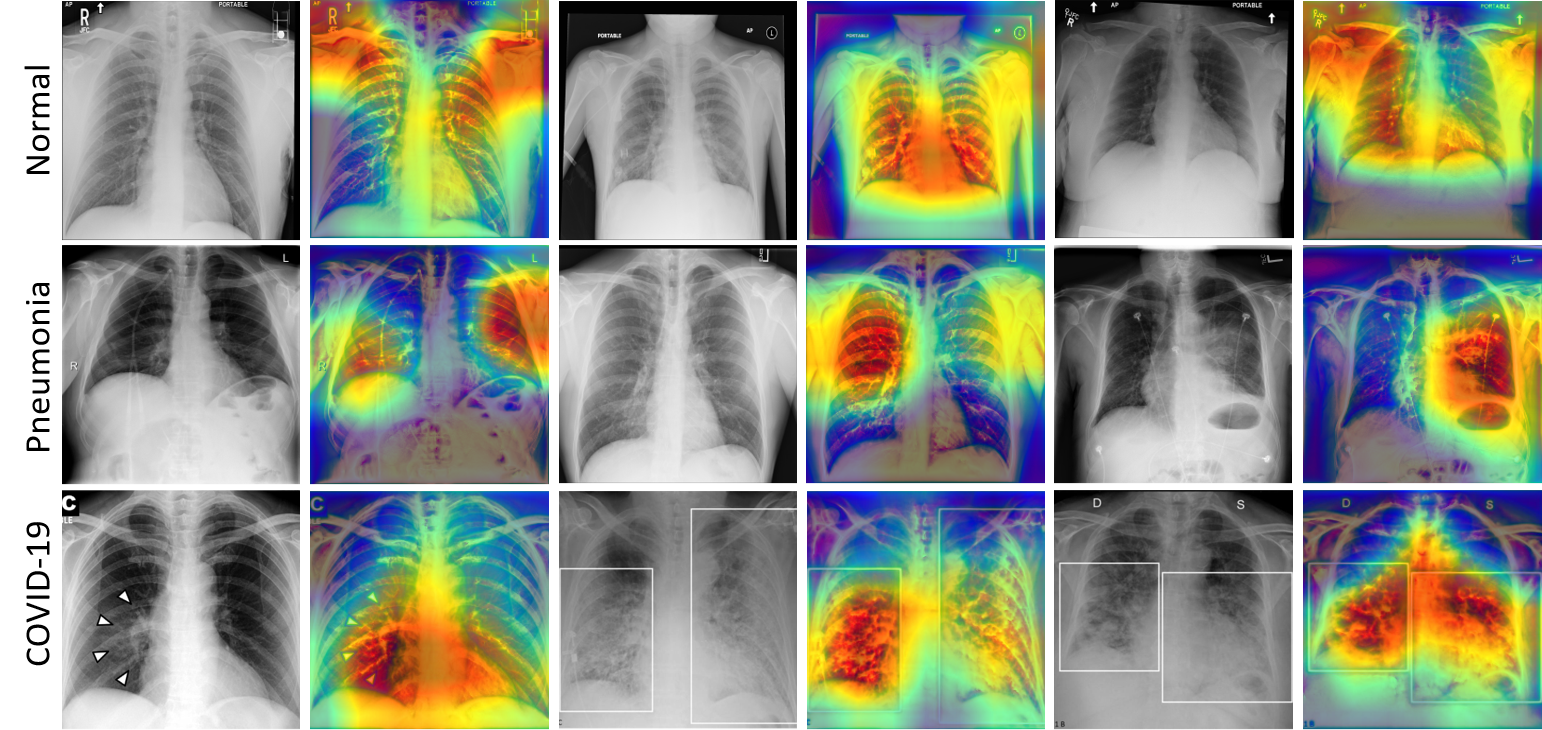

Gradient-weighted Class Activation Mapping (Grad-CAM) Selvaraju_2019 visualization of normal, pneumonia, and COVID-19 are presented as qualitative results in Figure 4. Investigating Figure 4 we can see the discriminative regions of interest localized in the normal, pneumonia, and COVID-19 data.

Refer to caption

Figure 4: Grad-CAM images Selvaraju_2019 obtained by late fusion ResNet50 architecture.